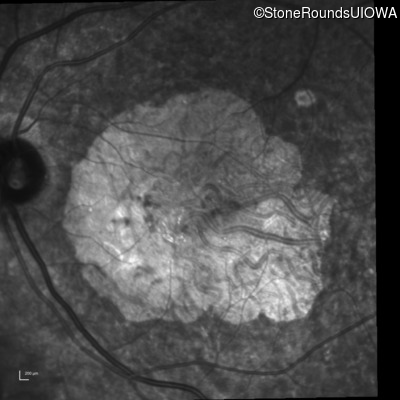

Infrared Fundus Photograph - Right - 20/200 sc

Exemplar

Infrared Fundus Photograph - Left - 20/200 sc